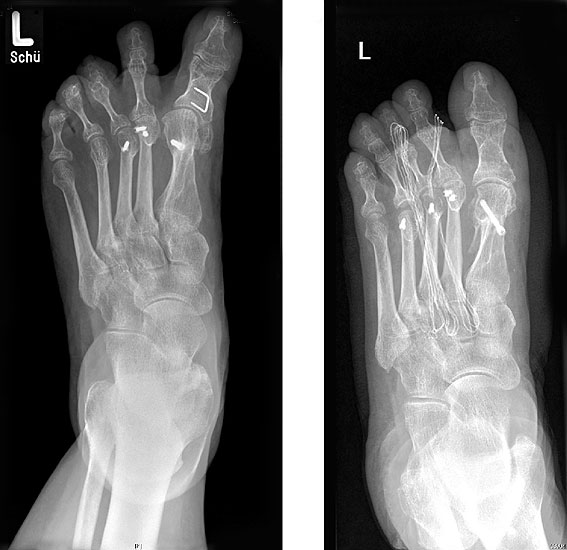

Radiologische Diagnostik

11"> Der Hallux varus Winkel  <a class=11" title="Der Hallux varus Winkel 11" srcset="/assets/images/2/4-vk3bypbg5s5x7zc.jpg 1x, /assets/images/3/4-aax2sd1hrpnrvrb.jpg 1.452x" width="270" height="240" loading="lazy">

Abbildung 3

Die bildgebende Diagnostik hilft bei der Klärung der Ätiologie und des Ausmaßes der Fehlstellung. Hierzu sind Röntgen­aufnahmen im Stand in mindestens zwei Ebenen unter Belastung des Fußes erforderlich. Mit Hilfe der belasteten Röntgenaufnahmen wird der Hallux-varus-Winkel, d. h. den Winkel zwischen der Achse der Grundphalanx der Großzehe und der Achse des ersten Mittelfußknochens bestimmt, sowie etwaige Rotationsfehlstellungen des 1. Strahls verifiziert. Eventuelle knöcherne Fehlanlagen bei kongenitalen Deformitäten können hierdurch ebenfalls verifiziert werden.

Weitere Beurteilungskriterien sind:

• degenerative Veränderungen des MTP I

• Kongruenz des MTP I- Gelenkes

• Form und Stellung des Mittelfußköpfchens I

• Ausprägung der Pseudoexostose.

• PASA-Winkel, d. h. der periphere Artikulationswinkel des Großzehengrundgelenkes.

Zur Klärung der Ätiologie wird der intermetatarsale Winkel zwischen Os metatarsale I und II bestimmt. Ist dieser kleiner als 5° oder gar negativ, ist eine Varusstellung der Großzehe oft die Folge.

Am Röntgenbild des belasteten Fußes bestimmt man die Lage der Sesambeine zum 1. Mittelfußköpfchen.

Anhand der Röntgenaufnahme lassen sich die Folgen einer eventuellen Voroperation bestimmen, wie z. B. die Stellung des ersten Mittelfußköpfchens, des ersten Metatarsale nach Korrekturen der Achse bei einer Hallux-valgus-Operation. Mitunter bestehen Nekrosen des Mittelfußköpfchens oder eine übermässige Resektionen der Pseudoexostose. Auch die Länge des 1. Metatarsale kann von Interesse sein, z. B. nach einer Lapidusarthrodese (Johnson 1994).

Bei Unsicherheiten der Genese kann als weiterführende Diagnostik ein CT oder MRT indiziert sein 121314.